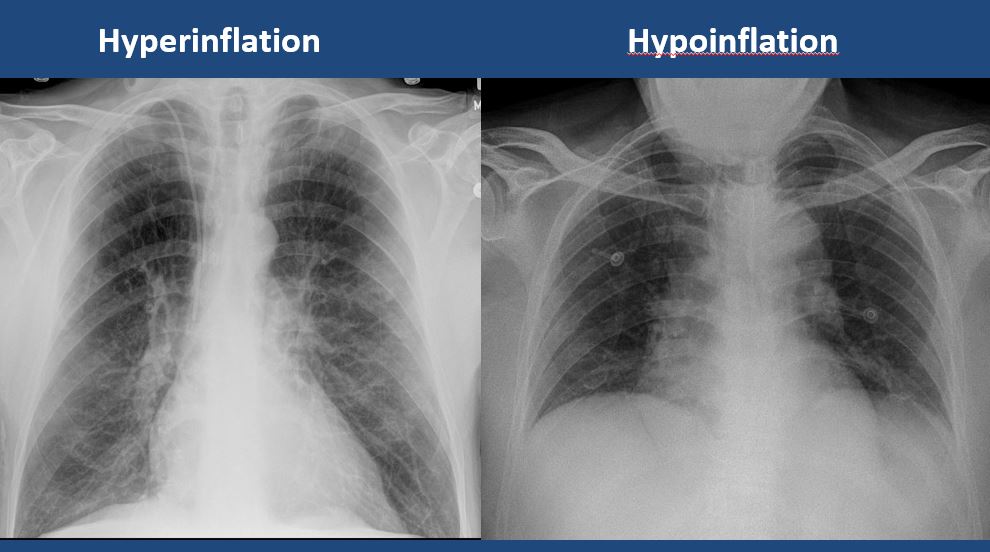

The lungs are hyperinflated or underinflated. [Yes/No]